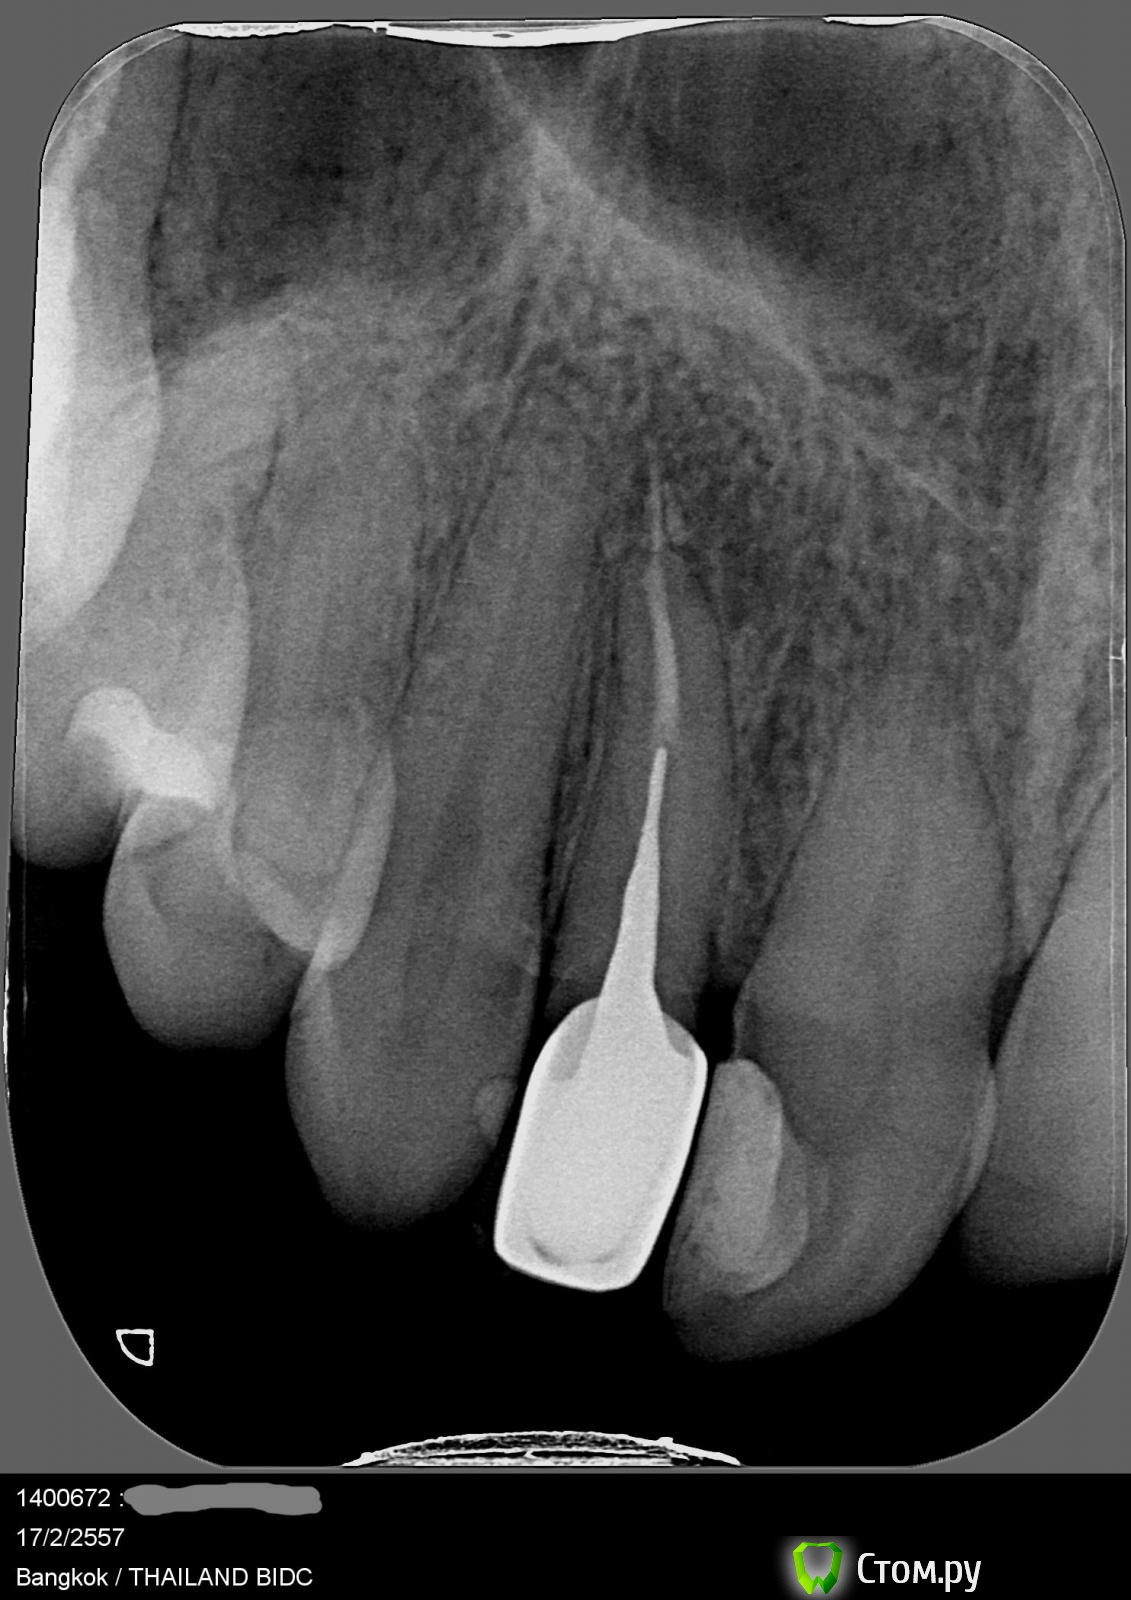

Правый верхний первый резец. Оказалось, что под пломбой полость. Стоматолог сказала, что полость большая и что по рентгену ей непонятно насколько близко она подходит к нерву и станет понятно только после того, как пломбу вытащат и полость почистят. Если полость подходит не близко, то зуб просто заново запломбируют. При этом варианте по ее предварительной оценке это поможет на год примерно и что лучше все-таки сразу поставить коронку. Я так поняла, что это потому что зуб передний, тонкий и при такой большой полости гарантий того, что все будет держаться, мало. Если полость подходит близко к нерву и затронут канал, то по ее словам нужно будет лечение канала и потом ставить коронку.

Правый верхний второй резец. Штифт для коронки и первую коронку мне ставили в небольшом российском городке в 2006 году, было долгое воспаление, неудобная коронка, которая замедляла восстановление. Потом в 2008 в Москве я меняла коронку, но штифт не меняла. Коронка стала удобная, но все равно периодически были воспаления, которые были видны на рентгенах. Мне всегда говорили, что воспаление мелкое, ничего страшного, или что можно в крайнем случае попить антибиотики.

Сегодняшние результаты (февраль 2014) - то, что мне сказала стоматолог. Между коронкой и корнем зуба есть полость, и есть воспаление на остатке корня (в самой глубокой его части - там где оно и раньше обнаруживалось). Варианты лечения этого зуба, которые она предложила: снять коронку и штифт, проверить насколько сильный этот остаток корня. Если сильный, то пролечить канал, вставить новый штифт и новую коронку. Если остаток слабый, то ставить мост или имплант. По мнению этого врача остаток корня на снимках выглядит так, что даже если он сильный, то коронка простоит лет 5, а дальше уже как повезет.

post-37722-0-76547700-1392636438_thumb.jpg